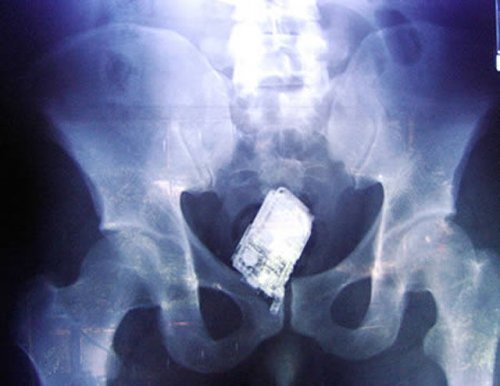

На рентгеновском снимке виден мобильный телефон в нижнем отделе кишечника заключенного из Сальвадора. Мужчина был одним из четырёх заключенных членов уличной банды Мара Салватруча (Mara Salvatrucha). Работники тюрьмы Закатеколука (Zacatecoluca) Сан-Сальвадора (San Salvador) задержали мужчин с контрабандными мобильными телефонами, запасными SIM-картами и зарядными устройствами.